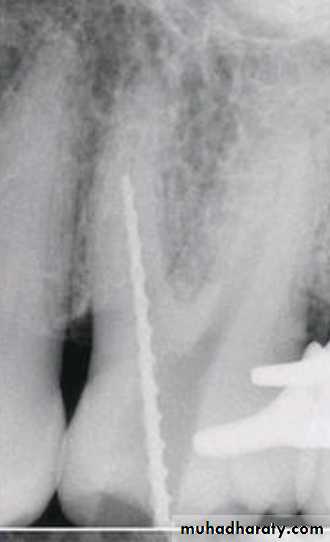

Step-back technique

MAF

WL – 0.5 mm

WL=21

SIZE=25WL=20.5

SIZE=30

WL=20

SIZE=35

WL=19.5

SIZE=40

WL=19

SIZE=45

WL=18.5

SIZE=50

WL=18

SIZE=55

WL=17.5

SIZE=60

WL=17

SIZE=70